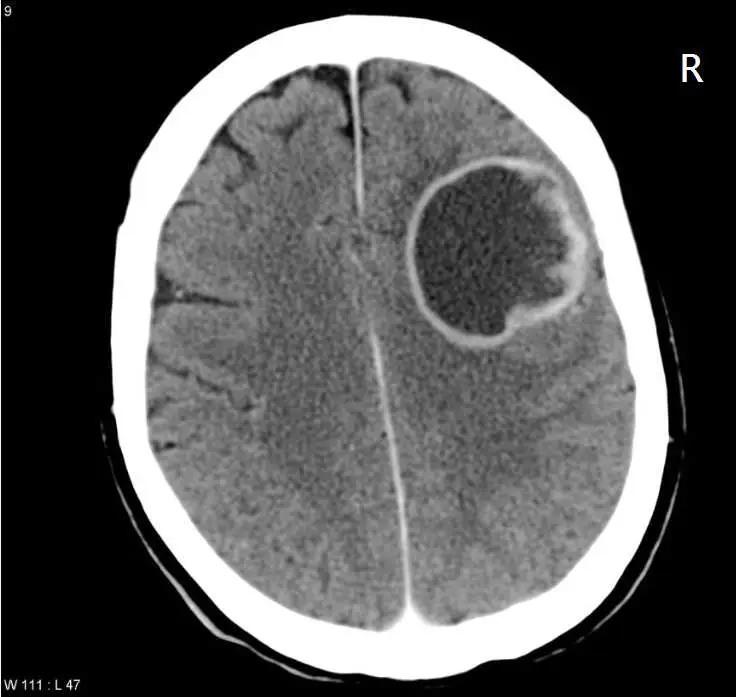

王老太太因腦部感染入院, MRI 中出現如圖中一個指環狀的病灶,則其可能的診斷為何?

影像為腦部橫斷面 CT 掃描(W111: L47,右側標記 R),可見右側大腦半球(影像左側,對應解剖右側)出現一個大型圓形低密度病灶,直徑約 4–5 cm,具有以下特徵:

- 指環狀高密度邊緣(ring-enhancing pattern):病灶周邊有明顯高密度環形邊界,代表膿瘍壁(abscess capsule)的血腦屏障破損及炎性包膜

- 中央低密度區:代表液化壞死的膿液(pus)所在

- 周圍低密度暈圈:病灶周邊腦組織的血管性水腫(vasogenic edema)

- 佔位效應:右側半球受壓,腦室輕度變形,中線結構輕度向左偏移

此典型「指環狀病灶」(ring sign)為腦膿瘍的特徵性影像表現,與本題臨床情境(腦部感染)高度吻合。